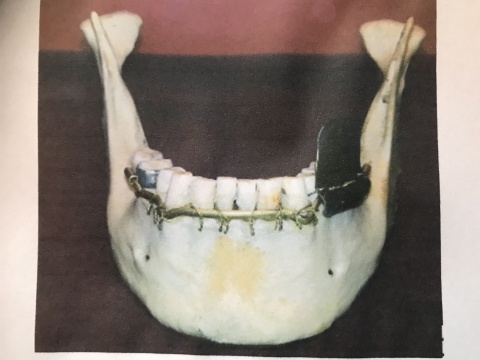

Zur Anwendung kamen bevorzugt dentale Drahtschienenverbände, in der Regel nach dem Prinzip von SCHRÖDER [8,15] die von den Zahnärzten als Immediatschiene ohne große technische Hilfsmittel sofort im Feldlazarett angelegt werden konnten. Im zahnärztlichen Feldgerät [2] war zum Einen das Werkzeug für diese Verbände schon recht frühzeitig, so ab Ende 1914 vorhanden, aber auch eine Grundausstattung an Material an Drahtschienen, Ligaturendraht, Häkchen, vorgefertigter schiefer Ebenen und Lötmaterial, wie es der Packliste des zahnärztlichen Geräts zu entnehmen ist [2]. Diese Schienen waren primär als Drahtligaturenverbände konzipiert. Sie bestanden aus einem starren Schienungsdraht, der entweder direkt am Patienten oder an einem Modell nach Gipsabdruck gebogen wurde. Dieser wurde dann mit Drahtligaturen aus dünnem, sehr flexiblen Draht an den Zähnen befestigt . (Siehe Abb. 4)